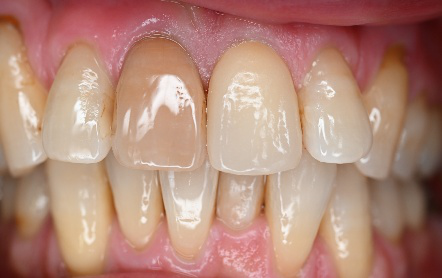

右の1本は、被せ物をしていましたが、すり減り形が変わり、変色もしていました。他の3本はすでに神経がない状態で、詰め物をしていましたが、詰め物及び歯自体も変色し、詰め物と自分の歯の境目のところからむし歯になっていました。治療後「きれいになって嬉しいです。治療して本当に良かったです。」と、とても喜んでくださいました。

オールセラミック冠4本:¥104,500×4本=¥418,000(税込)

Before

After